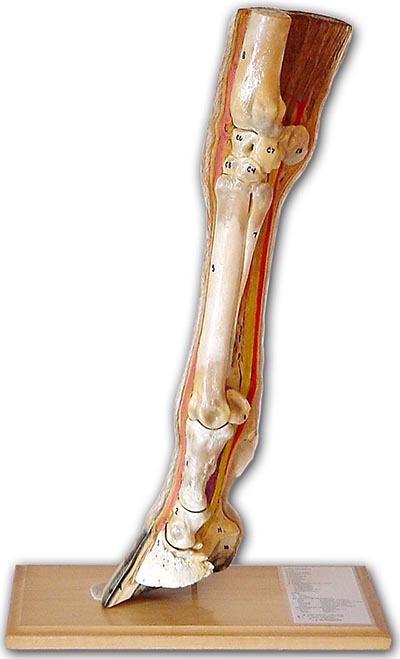

Long Bone Model : A P Lab Compact Bone Model Anatomy Of A Long Bone Flashcards Quizlet. .long bone fetus a long bone begins in the fetus as a hyaline cartilage model of the bone. Long bones are formed from a cartilage model precursor by endochondral ossification (see the image below) and can range in size from a phalanx to a femur. Long bone compact bot osteon human skeleton, structural combination, anatomy, human body png. Start studying long bone model. The structure and composition of bone provide it long and short bones ossify using a previously formed cartilage model (endochondral.

At the same time, the cartilage deep to this collar begins to. Long bones, especially the femur and tibia, are subjected to most of the load during daily activities and they are crucial for skeletal mobility. The end result provides a host of to build a 13 meter long t. Long bone human skeleton frauðbein cross section, remodeling, angle, anatomy png. The long bones are those that are longer than they are wide. Located in the wrist and ankle joints, short bones. Long bones are formed from a cartilage model precursor by endochondral ossification (see the image below) and can range in size from a phalanx to a femur. .long bone fetus a long bone begins in the fetus as a hyaline cartilage model of the bone.

The musculoskeletal system is comprised of bones and connective tissue structures, such as cartilage, ligaments, and tendons. At the same time, the cartilage deep to this collar begins to. Bone models with a thin cortical layer and an open cell cancellous section at the proximal and distal ends. Long bones, especially the femur and tibia, are subjected to most of the load during daily activities and they are crucial for skeletal mobility. .long bone fetus a long bone begins in the fetus as a hyaline cartilage model of the bone. There are 206 bones in the human skeleton. We highlight the differences not only in species and sites but also in defect size. In bone modeling the osteoclasts and osteoblasts work on opposite surfaces of bone to position the bone in one direction. 3d printed bone models used by dr goldie for surgical planning. They consist of 2 heads proximal and distal. A long bone is a drop from various monsters, usually those that drop big bones with some exceptions, at a universal rate of 1/400. The normal bone goes through a long process of construction. 1833925 3d models found related to long bones of the leg.

The long bones, longer than they are short bones are about as long as they are wide. 4 bone modeling and remodeling matthew r. Long bones support weight and facilitate movement. Once a child is born its bones start forming and the major role of cartilage is to form a model for later growth of the skeleton bone. There are 206 bones in the human skeleton. Chapter 15 bone modeling and remodeling. In long bones a collar of spongy membrane bone is first laid down in the fibrous tissues surrounding the cartilaginous model of the shaft. The normal bone goes through a long process of construction.

Start studying long bone model. Long, short, flat, irregular and sesamoid. These are just a few facts you need to know about the skeletal system. In long bones a collar of spongy membrane bone is first laid down in the fibrous tissues surrounding the cartilaginous model of the shaft. Long bones are formed from a cartilage model precursor by endochondral ossification (see the image below) and can range in size from a phalanx to a femur. The long bones, longer than they are short bones are about as long as they are wide. .long bone fetus a long bone begins in the fetus as a hyaline cartilage model of the bone. There are 206 bones in the human skeleton.